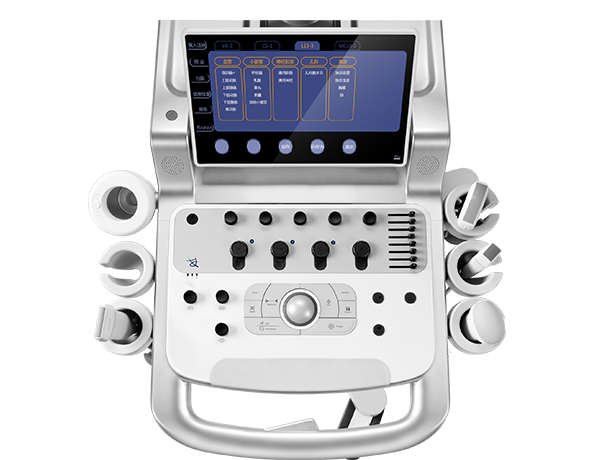

科学操作面板 精简设计

电动升降可旋转操控面板

电动升降可旋转操控面板 简约界面 科学布局

简约界面 科学布局 -